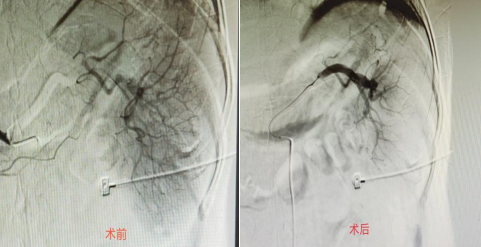

近日,我院普外二科再次应用介入治疗手段为一名综合情况极差的患者实施了部分性脾动脉栓塞术(PSE)。该患者因脾亢入院,入院时实验室检查提示三系减少,血小板最低仅19*10^9/L(正常水平100-300*10^9/L),异位出血风险极高,同时患者3个月前曾突发脑梗致言语及右侧肢体活动受限,既往有肺结核病史,1个月前感染新冠。患者病情危急且一般综合情况极差,经叶临生主任、胡永毅副主任及科内同仁严密讨论后决定行部分性脾动脉栓塞术。手术由朱珲副院长、陈诚主治医师手术团队在介入中心顺利完成,术中神经内科盛守权主任全程为病人保驾护航。

手术过程中,经皮肤穿刺股动脉后,插入一根直径约1.5mm的导管,在DSA引导下,将导管插入脾动脉,再经微导管注入适量特制的PVA栓塞颗粒,栓塞住脾脏一部分小动脉,使相应部位的脾组织缺血、梗死、固缩,进入脾脏的血液减少。这样既纠正了脾功能亢进,又保留了正常的脾脏功能,且术后第二天即可下床活动,具有损伤小、恢复快、可重复治疗等优势,目前患者血小板已从术前的19*10^9/L上升至91*10^9/L,获得了患者及家属的高度赞誉!